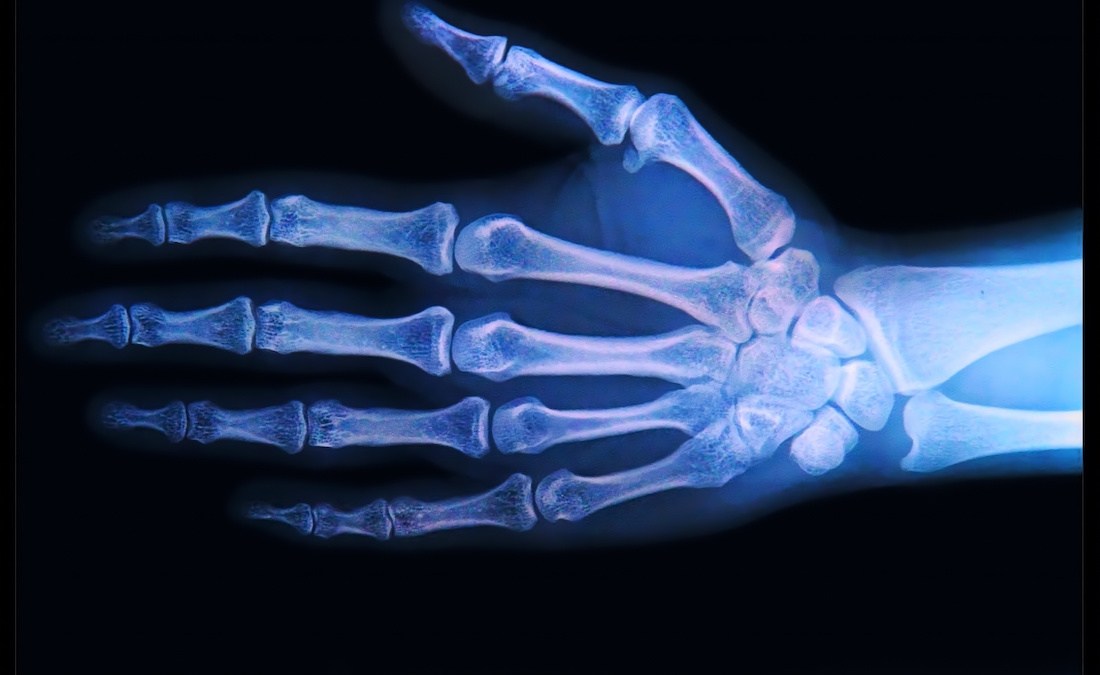

What does a Mesozoic dinosaur unearthed in Kansas have in common with John the Baptist and hundreds of millions of people worldwide have in common? Osteoarthritis. Not to be confused with its sister diseases, rheumatoid arthritis (inflammation caused by autoimmune reaction in the joints) and osteoporosis (the gradual weakening of bones), osteoarthritis (OA) is the gradual thinning of the articular cartilage — the smooth, lubricating connective tissue that covers the ends of bones at a joint. Articular cartilage provides pain-free movement at the joints, at least when it’s healthy.

When cartilage becomes damaged and thin, bond grinds against bone. In some patients, you can actually hear a crackling noise as the bones grate against each other. Over time, the friction wears down the bone until nerve ends are exposed, and everyday movements — walking, sitting, even writing — result in excruciating pain.